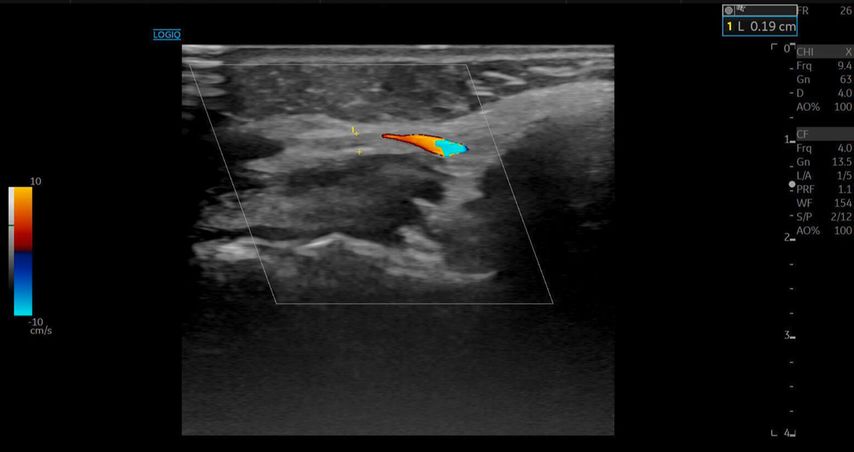

Die A. facialis imponierte beim Austritt im Bereich des Musculus masseter (oberhalb der Kieferlinie) vasospastisch mit einem maximalen Durchmesser von 1mm. Die abgeleitete systolische Spitzengeschwindigkeit betrug trotz der bestehenden Ischämie 20cm/s, ohne enddiastolische Komponente, was auf eine weitere periphere Vasokonstriktion hindeutete (Abb. 2 und 3).

Die Duplexsonografie ergab folgende Befunde (Abb. 5 und Abb. 6):

Der Durchmesser der A. angularis und A. facialis hatte sich nahezu verdoppelt.

Die systolische Spitzengeschwindigkeit (PSV) stieg von 20cm/s auf über 100cm/s.

Die enddiastolische Geschwindigkeit (EDV) betrug nun 20cm/s, was auf eine periphere Vasodilatation und eine Wiederherstellung der Makrozirkulation hindeutete (Abb. 7).